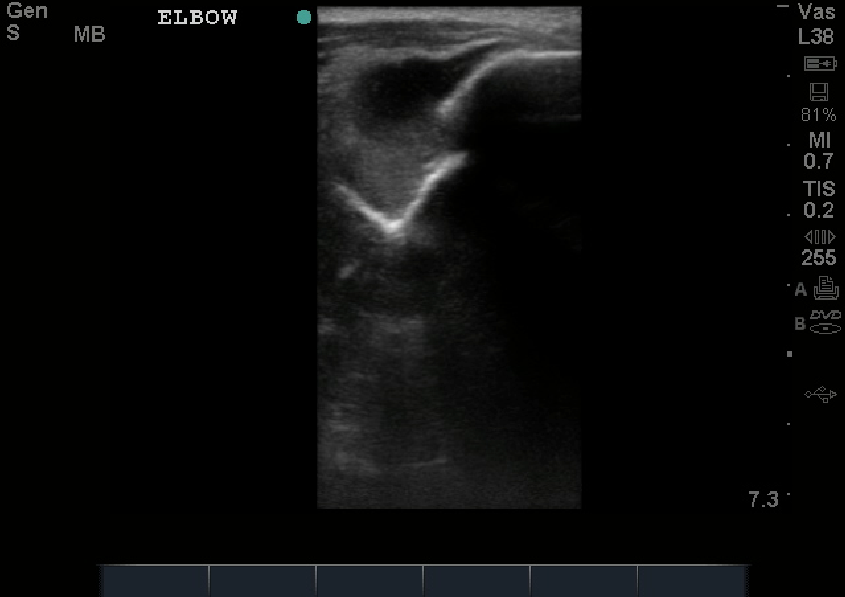

This was a prospective observational study. A convenience sample of patients suspected of having shoulder dislocation was enrolled in the study. Ultrasonography was performed before and after reduction procedure with a 7.5- to 10-MHz linear transducer. Shoulder dislocation was confirmed by taking radiographs in 3 routine views as a criterion standard. The operating characteristics of ultrasonography to detect dislocation in patients with possible shoulder dislocation and to confirm reduction in patients with definitive dislocation were calculated as the primary endpoints.